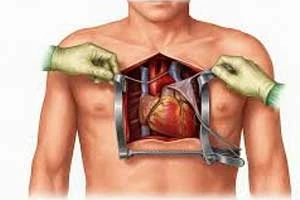

Open Heart Surgery

Comprehensive surgical procedures for complex heart conditions

Keyhole / Minimally Invasive Heart Surgery

Small incision surgery with faster recovery

Keyhole / Minimally Invasive Heart Surgery

Small incision surgery with faster recovery

Robotic Heart Surgery

Advanced robotic-assisted cardiac procedures